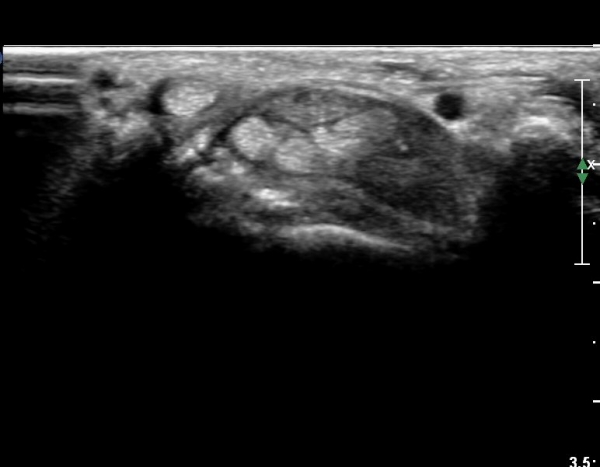

¼Õ¸ñ ºÎÀ§ Ⱦ´Ü¸é°Ë»ç¿¡¼ ¿ä°ñ°ú ¿ù»ó°ñ Àü¹æ¿¡ ¼®È¸È¼º À½¿µÀÌ Á¸ÀçÇϰí Àü¹ÝÀûÀÎ ¼öÁö ±¼°î°ÇÀÇ ºñÈÄ, Á¤Á߽ŰæÀÇ ºÎÁ¾°ú

ÈûÁÙ ¹× Á¤Á߽ŰæÀÇ Ç¥ÃþÀ¸·Î ÀüÀ§°¡ °üÂûµÈ´Ù, (»çÁø 1 ), ÆÄ¿öµµÇ÷¯°Ë»ç¿¡¼ Ç÷·ùÁõ°¡°¡ °üÂûµÊ´Ù(»çÁø 2)..